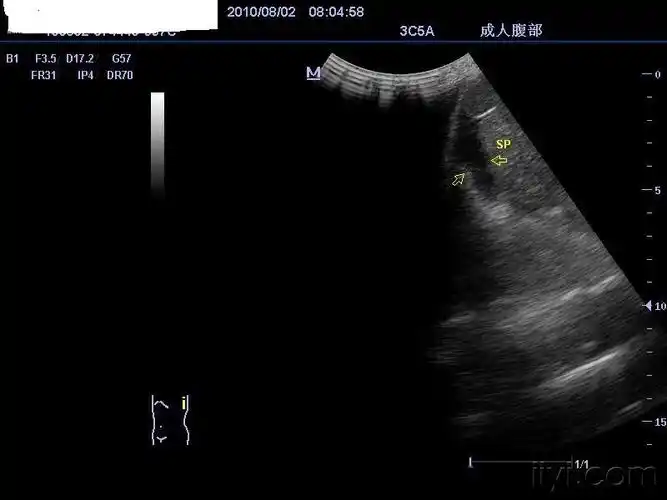

脾破裂(脾内血肿),脾周血肿

脾包膜下破裂.

【答案解析】_脾破裂声像图特征:①脾包膜,边缘不规则,连续中断②脾周